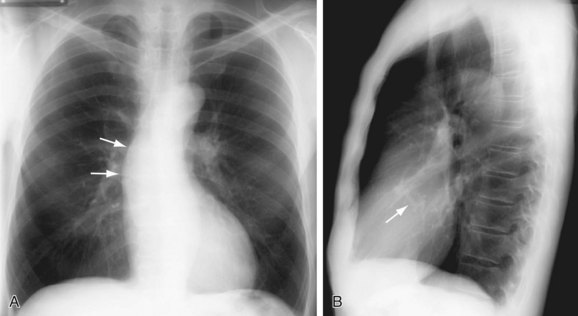

What is going on in this CXR?

These radiographs show atelectasis of the right middle lobe

You can tell that this is atelectasis rather than a consolidation by the downward displacement of the minor fissure

Fissures move towards a collapsed lobe, as do the trachea and heart, and the ipsilateral diaphragm.